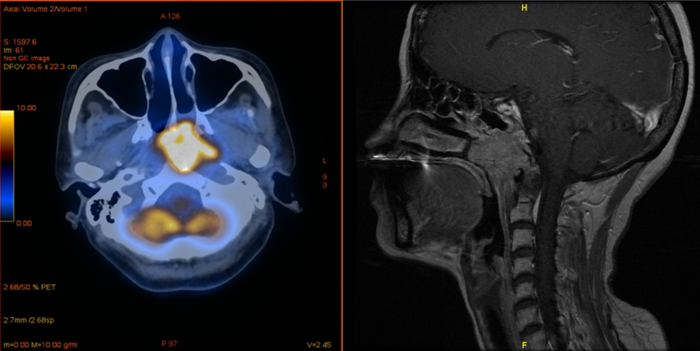

Tumores nasofaríngeos (em amarelo). (Fonte: Hua et al./Divulgação)

Como os imunizantes contra a covid-19 estimulam a resposta imune do organismo – explica ao EurekAlert o dr. Jian Li, do Hospital Universitário de Bonn –, "temia-se que a vacina não fosse compatível com a terapia antiPD-1”. A preocupação era maior no caso do “câncer de nasofaringe, que, como o vírus SARS-Cov-2, afeta o trato respiratório superior”.